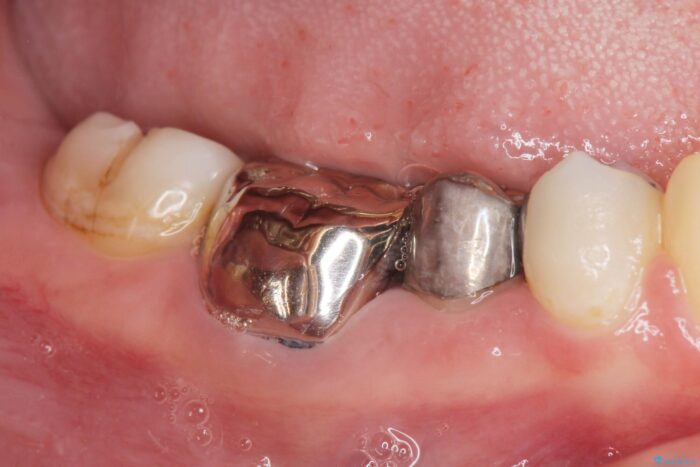

装着されていた清掃性の悪い銀歯を外すと、銀歯の下で歯ぐきよりも深い虫歯が再発していました。